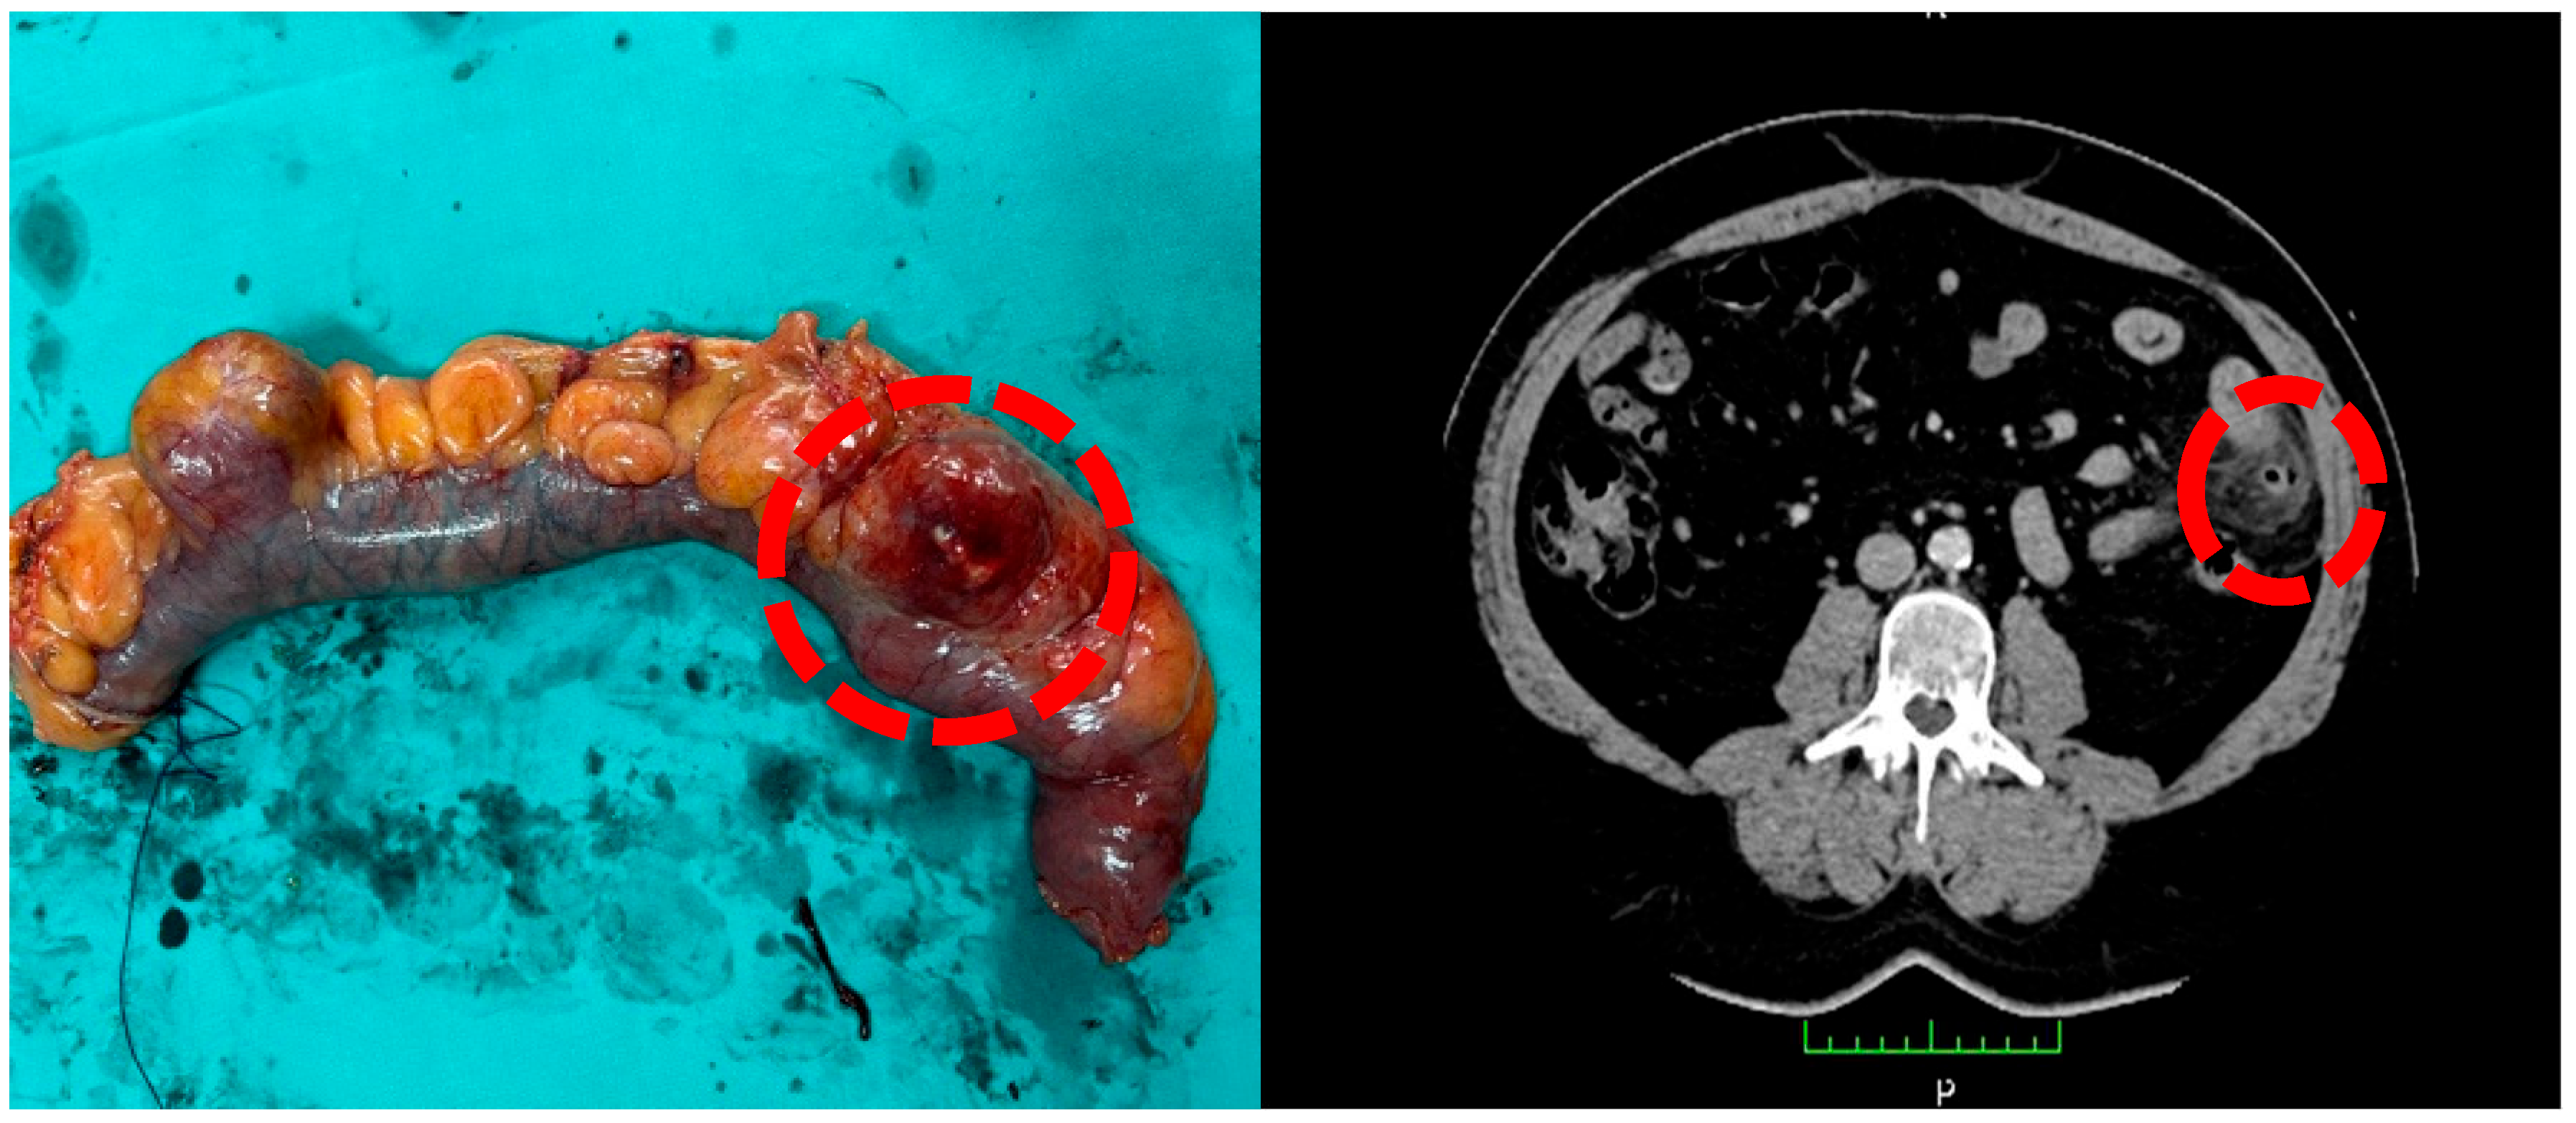

Case 1

Case 2